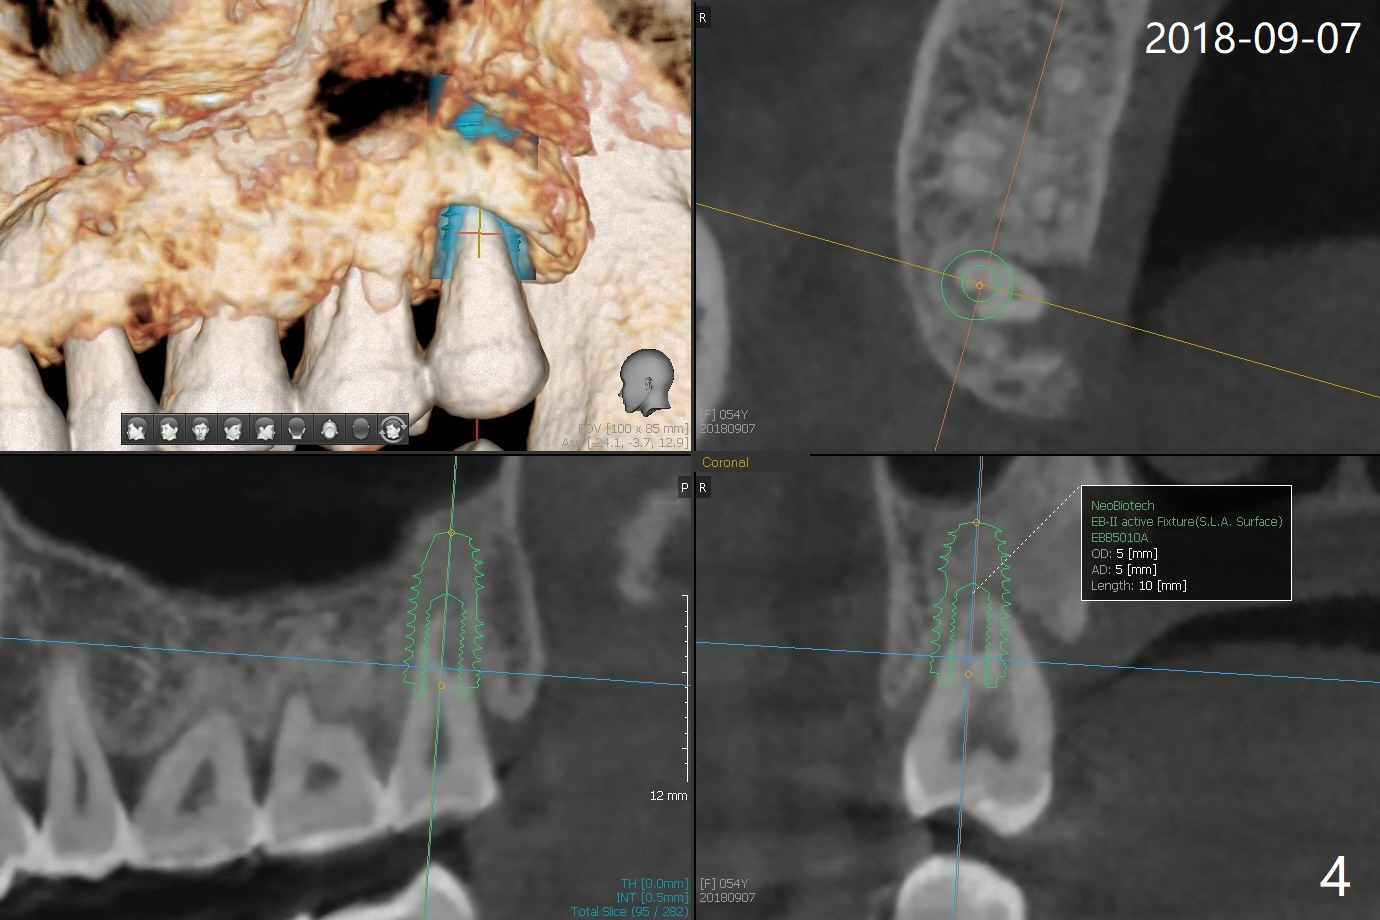

A 56-year-old woman returns to clinic with chief complaint of upper right discomfort (Fig.1) 9 months post #15 implant placement. Clinical exam does not reveal significant finding (periradicular radiolucency (PRRL) at #1 (*) is neglected). Six months later, PRRL at #1 is enlarged (Fig.2 *) with palatal gingival recession, pockets and BOP. The tooth is extracted; its palatal plate is lost, which is consistent with CT taken ~ 1 year earlier (Fig.3). Moreover, the palatal root is incidentally found to be have fractured at #2 (Fig.3,5 *), in the same manner as the tooth #15. Bone loss and root fracture are related to bruxism. Since the tooth #32 is present, an immediate implant could have been placed at #1 (Fig.4).